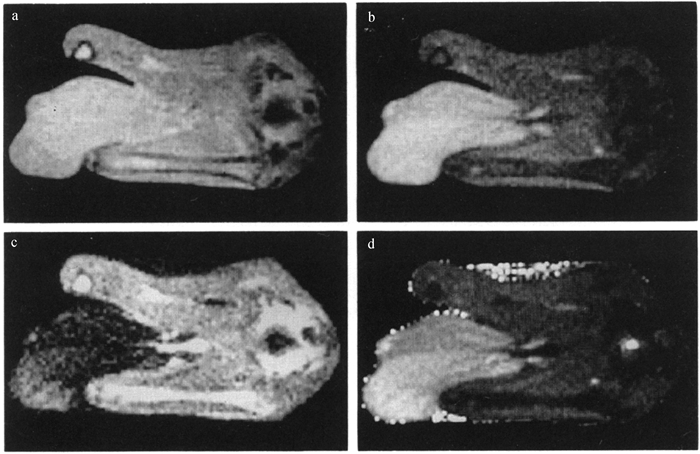

Fig. 4

Ultrasound detection images[75, 89] A. Ultrasound detection of mammary parenchyma; B. Ultrasound image of the right posterior mammary gland of a cow on day 75 of lactation; C. Ultrasound image of the right posterior mammary gland of a cow on day 7 of dry milking; D. Echotexture analysis of the mammary ultrasound image; E. Ultrasound image of mammary gland of calf at 8 weeks of age. White circle. Mammary parenchyma (hypoechoic); asterisks. Mammary fat pads (hyperechoic); dotted line. Marking of the body wall"

Fig. 5

Mammary vein frequency Doppler examination of cows[75] A. Blood flow characteristics of the mammary veins of cows on day 14 of lactation; B. Blood flow characteristics of the mammary veins of cows on day 35 of dry milking; C. Distance, diameter, and cross-sectional area of the mammary veins from the surface of the skin; D. Mammary localization position of the Doppler imaging probe"